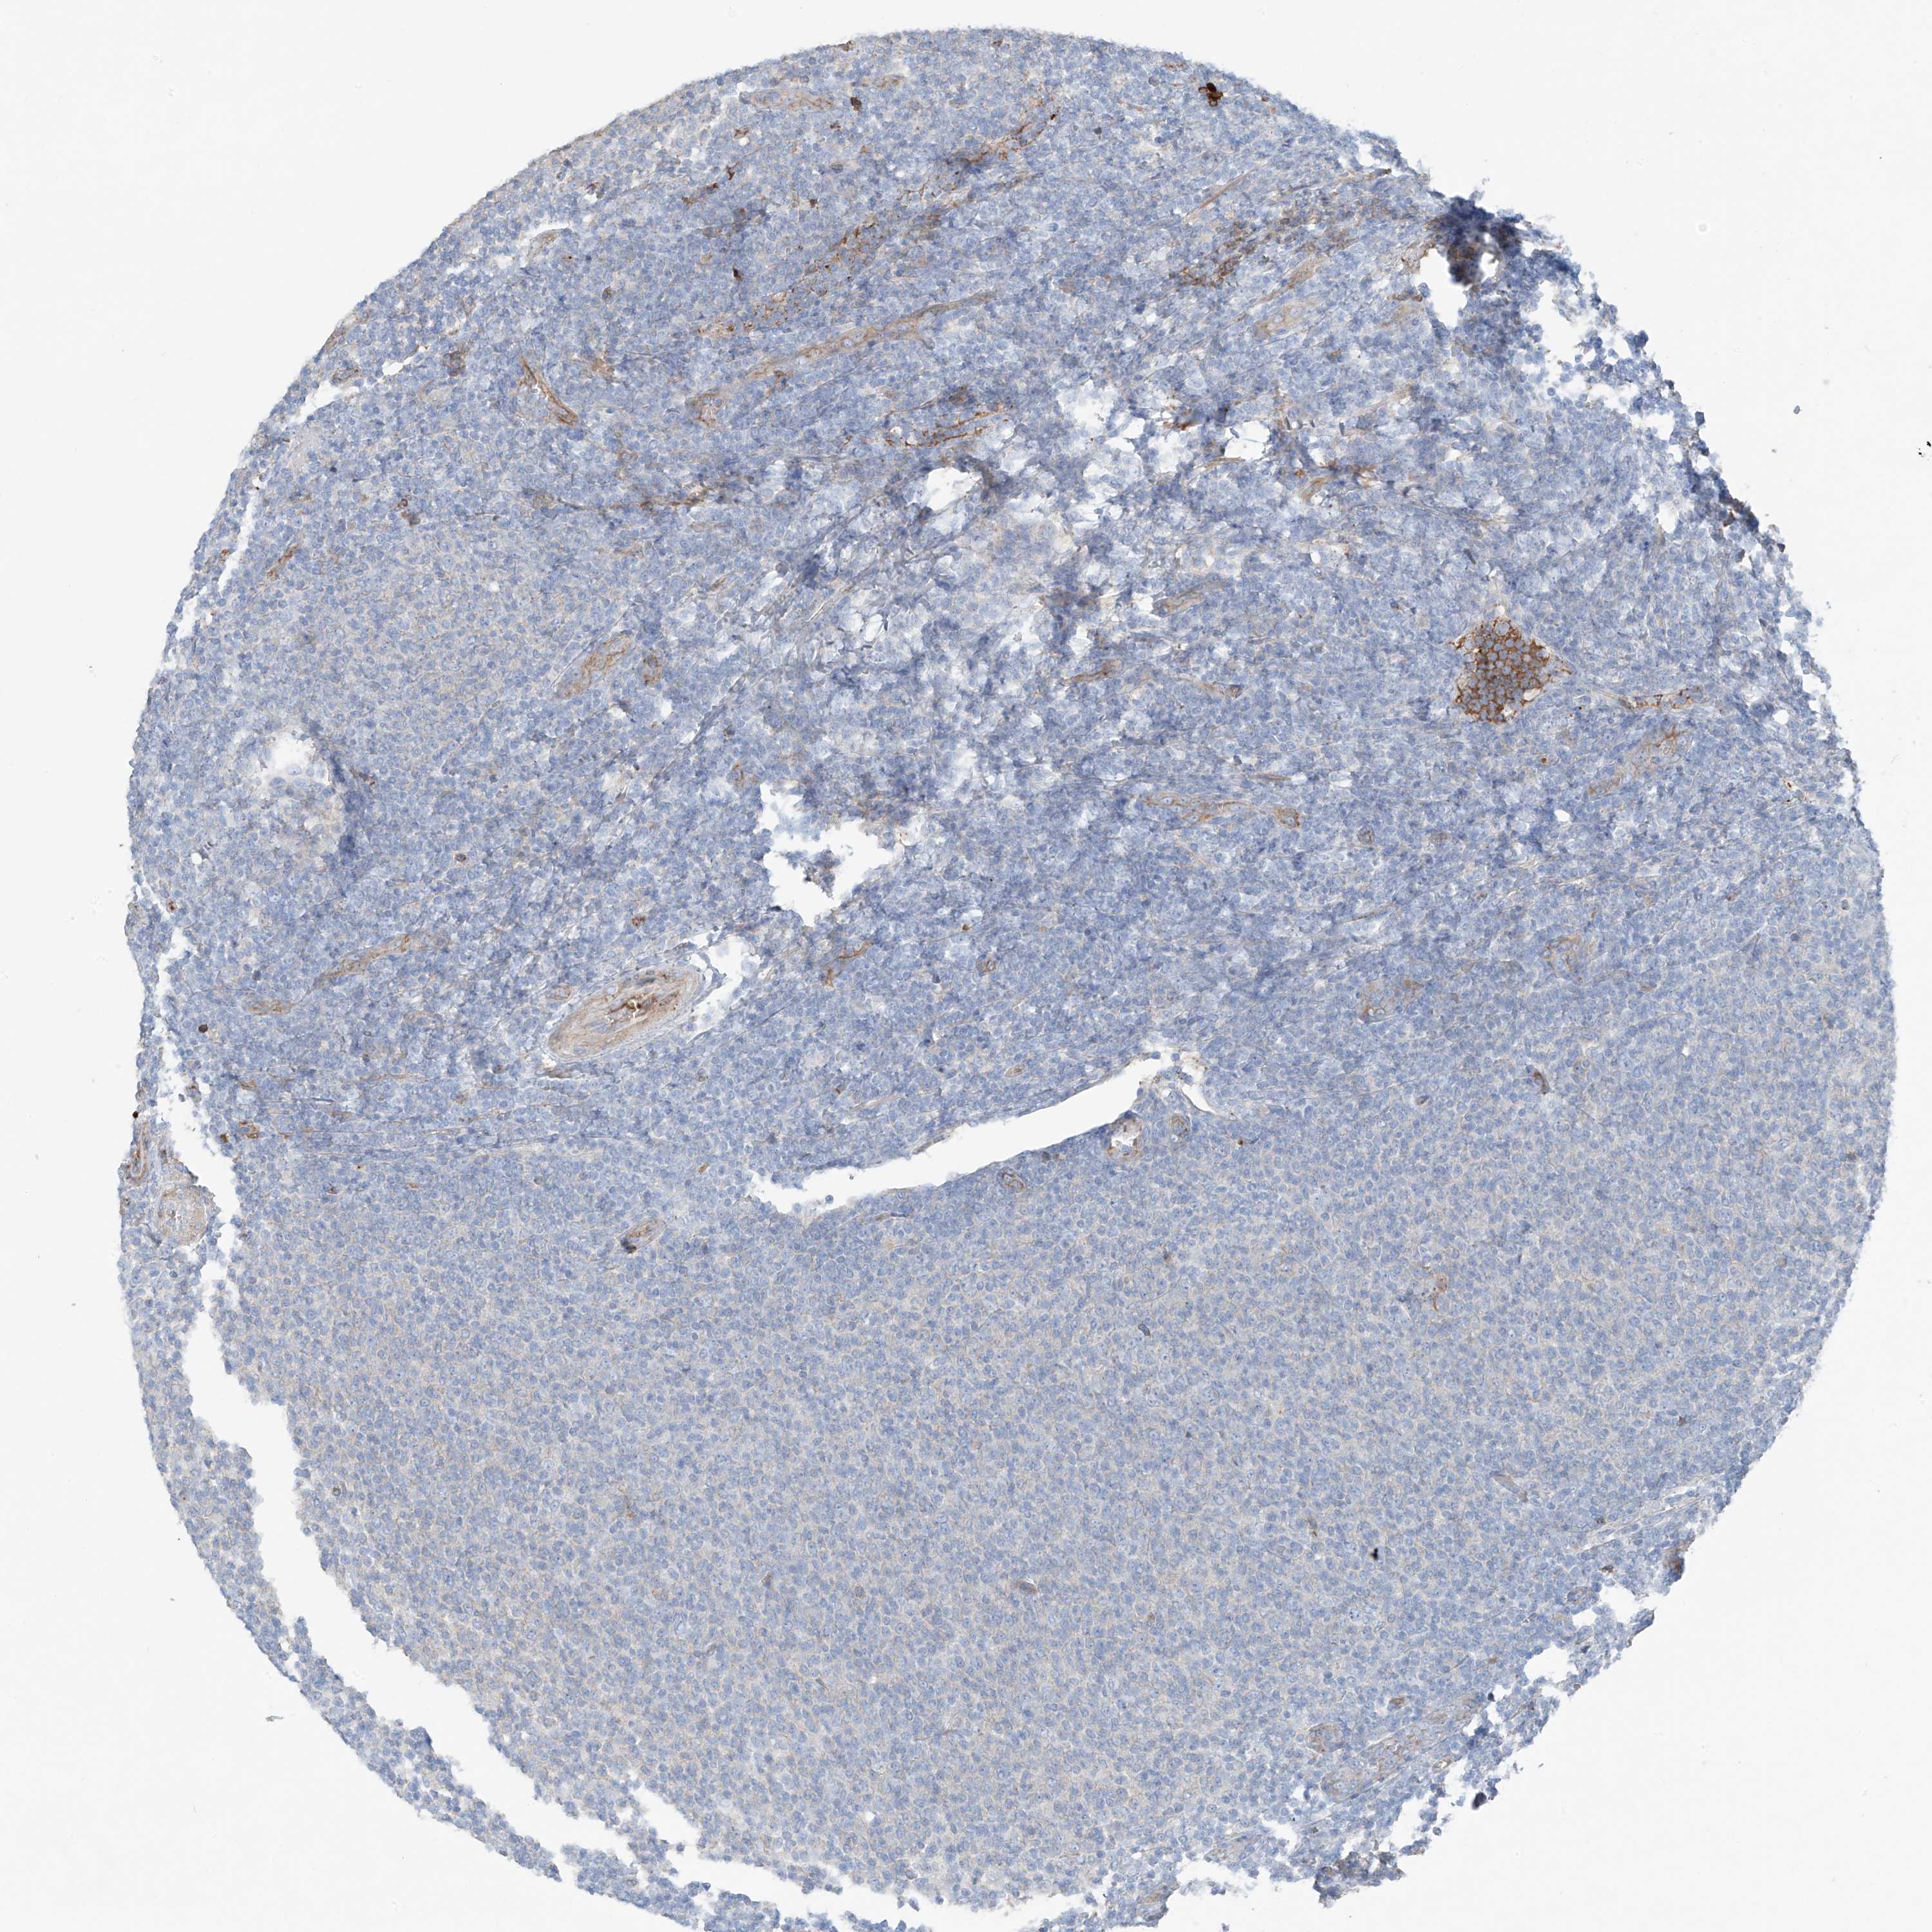

CANCER LYMPHOMA Show tissue menu

LYMPHOMA - Protein expressioni

A mouse-over function shows sample information and annotation data. Click on an image to view it in a full screen mode. Samples can be filtered based on level of antibody staining by selecting one or several of the following categories: high, medium, low and not detected. The assay and annotation is described here.

Each image is clickable and will lead to virtual microscopy that enables deeper exploration of all samples and also displays staining intensity scores, fraction scores and subcellular localization as well as patient and tissue information for each sample.

Antibody HPA009134

Staining

High

Medium

Low

Not detected

Intensity

Strong

Moderate

Weak

Negative

Quantity

>75%

75%-25%

<25%

None

Location

Nuclear

Cytoplasmic/membranous

Cytoplasmic/membranous,nuclear

Hodgkin's disease, NOS

Malignant lymphoma, non-Hodgkin's type, High grade

Malignant lymphoma, non-Hodgkin's type, Low grade